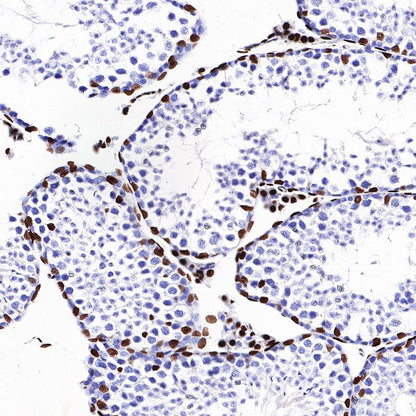

Immunohistochemistry

| IHC-P | 1:1000 | null |